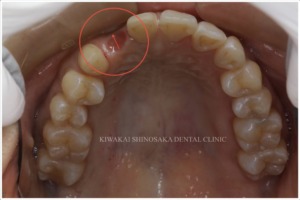

また詳しく診査・診断を行ったところ、折れてしまった箇所の歯肉が退縮していたため、どちらかの治療を選択されたとしても、歯肉の厚みを増やす【結合組織移植術(CTG)】を行う必要があることもお伝えいたしました。

その後、主訴である右上2の歯肉の厚さを増やすため、【結合組織移植手術(CTG)】を行いました。

また、歯茎下りによって右上4・5の歯の根が少し露出しており、滲みるなどの症状がみられましたので、同日に右上4・5への【結合組織移植を併用した根面被覆術】も行いました。

移植する結合組織は上顎から採取します。